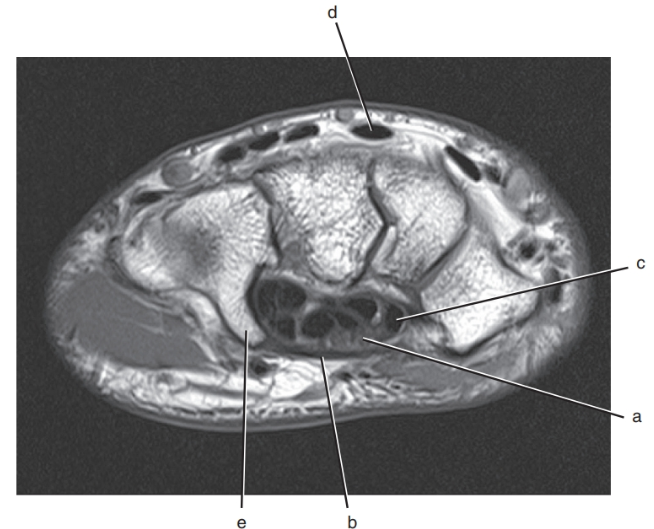

What is letter e ?

Hook of the hamate

Scaphoid

What is letter a?

Median nerve